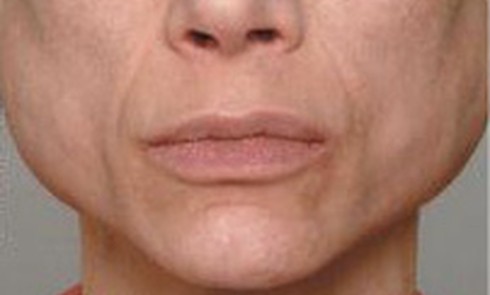

Outre les adolescents et jeunes adultes, davantage touchés par l’anorexie mentale, nos cabinets reçoivent un nombre non négligeable de patients...